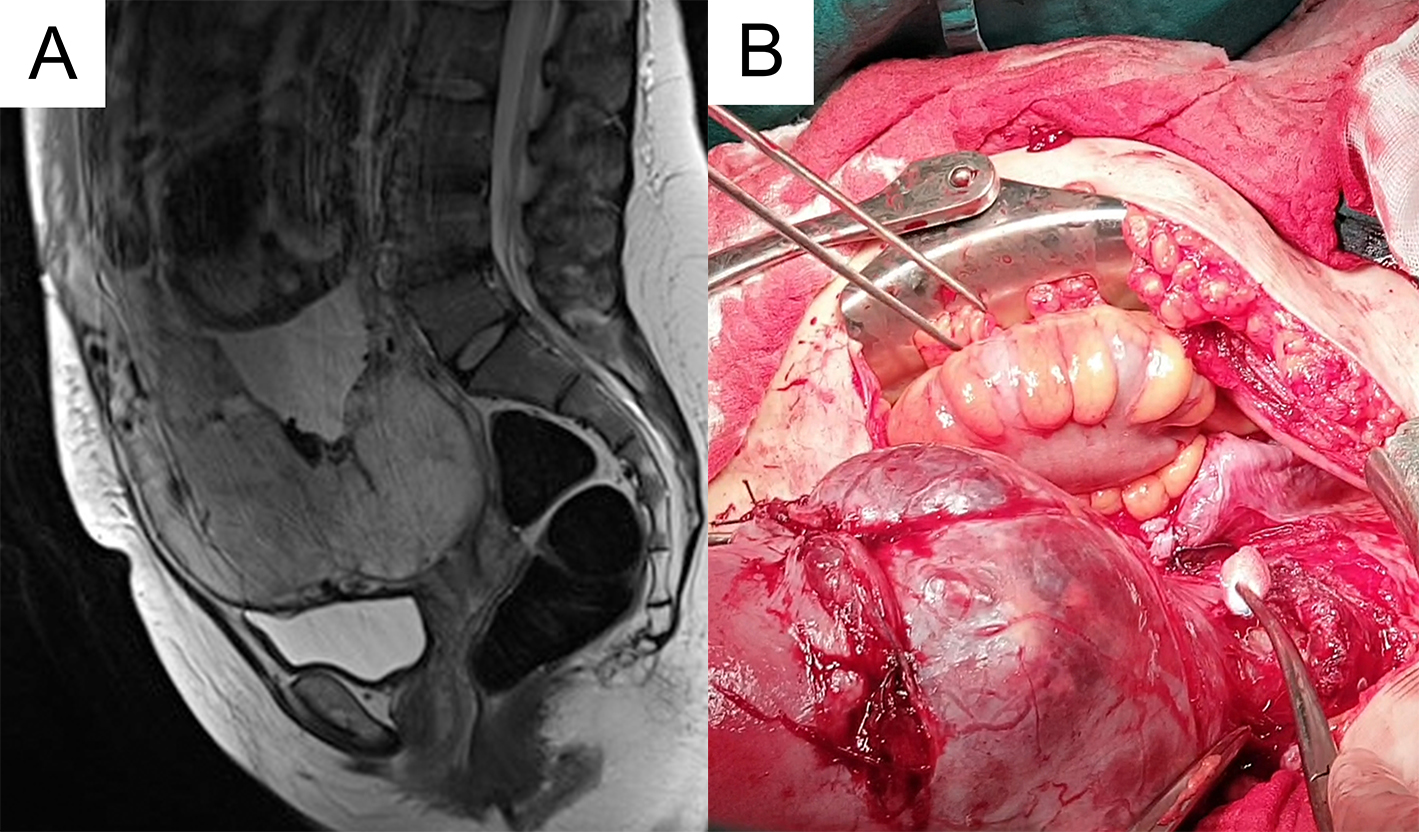

Woman, 29 years old (gravida 2) was referred to our clinical hospital centre due to the high-risk pregnancy. During a routine second-trimester examination, she was diagnosed with placenta previa and concomitant PAS disorder. Due to breech presentation, 18 months earlier, she had CS. Her medical history showed anaemia and she was a heavy smoker (20 cigarettes a day). On the day when she was admitted, she was in her 35th week. 2D transvaginal and transabdominal ultrasound showed the presence of irregularity of the hypoechoic plane in the myometrium under the placenta, multiple placental lacunae, loss in the retroplacental area, placental tissue was broken through the uterine serosa and was expanding to the posterior surface of the bladder. Colour Doppler showed tortuous vessels in the area of lower uterine segment and vessels spreading from the placenta over the myometrium and beyond the serosa into the bladder. Patient’s haemoglobin value was 98 and erythrocyte 2.98. Three days prior to the surgery, she received 600 mL allogeneic red blood cells, and she also antenatally received betamethasone for foetal lung maturation. Preoperative magnetic resonance imaging (MRI) confirmed placenta previa and percreta on the anterior wall of the uterus with specific features: loss of retroplacental “clear space”, a bulging of the placenta on the myometrium with its interruption and superficial invasion of the placental tissue into the bladder (Fig. 1). Cystoscopy was negative for infiltration. Both she and her husband were informed about the possible obstetric complications and the high probability of performing hysterectomy after delivering the baby. An elective caesarean section was performed in the 35th week of pregnancy. After the abdominal wall was opened by a median incision under the umbilicus, the inspection showedmany pelvic adherences, the presence of multiple outsized vessels at the level of the lower uterine segment and in the area of the bladder (Fig. 1). The placenta was bulky, reaching throughout the myometrium and extending to the posterior surface of the bladder. A transverse corporal hysterotomy was performed over the lower uterine segment with the purpose of avoiding placenta, and a healthy premature neonate weighing 2060 g was delivered. With the intention of reducing uterine bleeding during the surgery, the patient received tranexamic acid. Total hysterectomy and bilateral salpingectomy with the placenta in situ were done. The posterior wall of bladder was attached to the uterus; yet there was no deep invasion of placental tissue. After placing haemostatic sutures on the defect of bladder, the abdomen was inspected for bleeding; the operation was completed by placing the abdominal drain. In the course of the surgery, allogeneic red blood cells (800 mL) and fresh frozen plasma (890 mL) were transfused. The puerpera was admitted to the intensive care unit and received additional 600 mL allogeneic red blood cells and 600 mL fresh frozen plasma. The patient’s recovery was successful and she was discharged on the 7th postoperative day. The histopathological examination confirmed a placenta percreta.

Fig. 1.Preoperative magnetic resonance imaging and intraoperative findings. In the sagittal plane, sequence MR FIESTA T2 is visible placenta previa and superficial invasion in the bladder (A). The placenta was reaching throughout the myometrium and extending the posterior surface of the bladder (B).